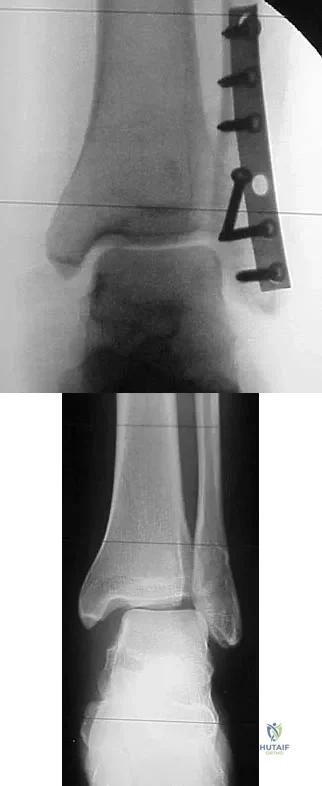

Question 82High Yield

A 64-year-old man with a history of diabetes mellitus underwent open reduction and internal fixation of a displaced ankle fracture 8 weeks ago. Examination now reveals recent onset erythema, warmth, and swelling of the midfoot. Radiographs are shown in Figures 23a through 23d. What is the most likely reason for the swelling of the foot?

Explanation